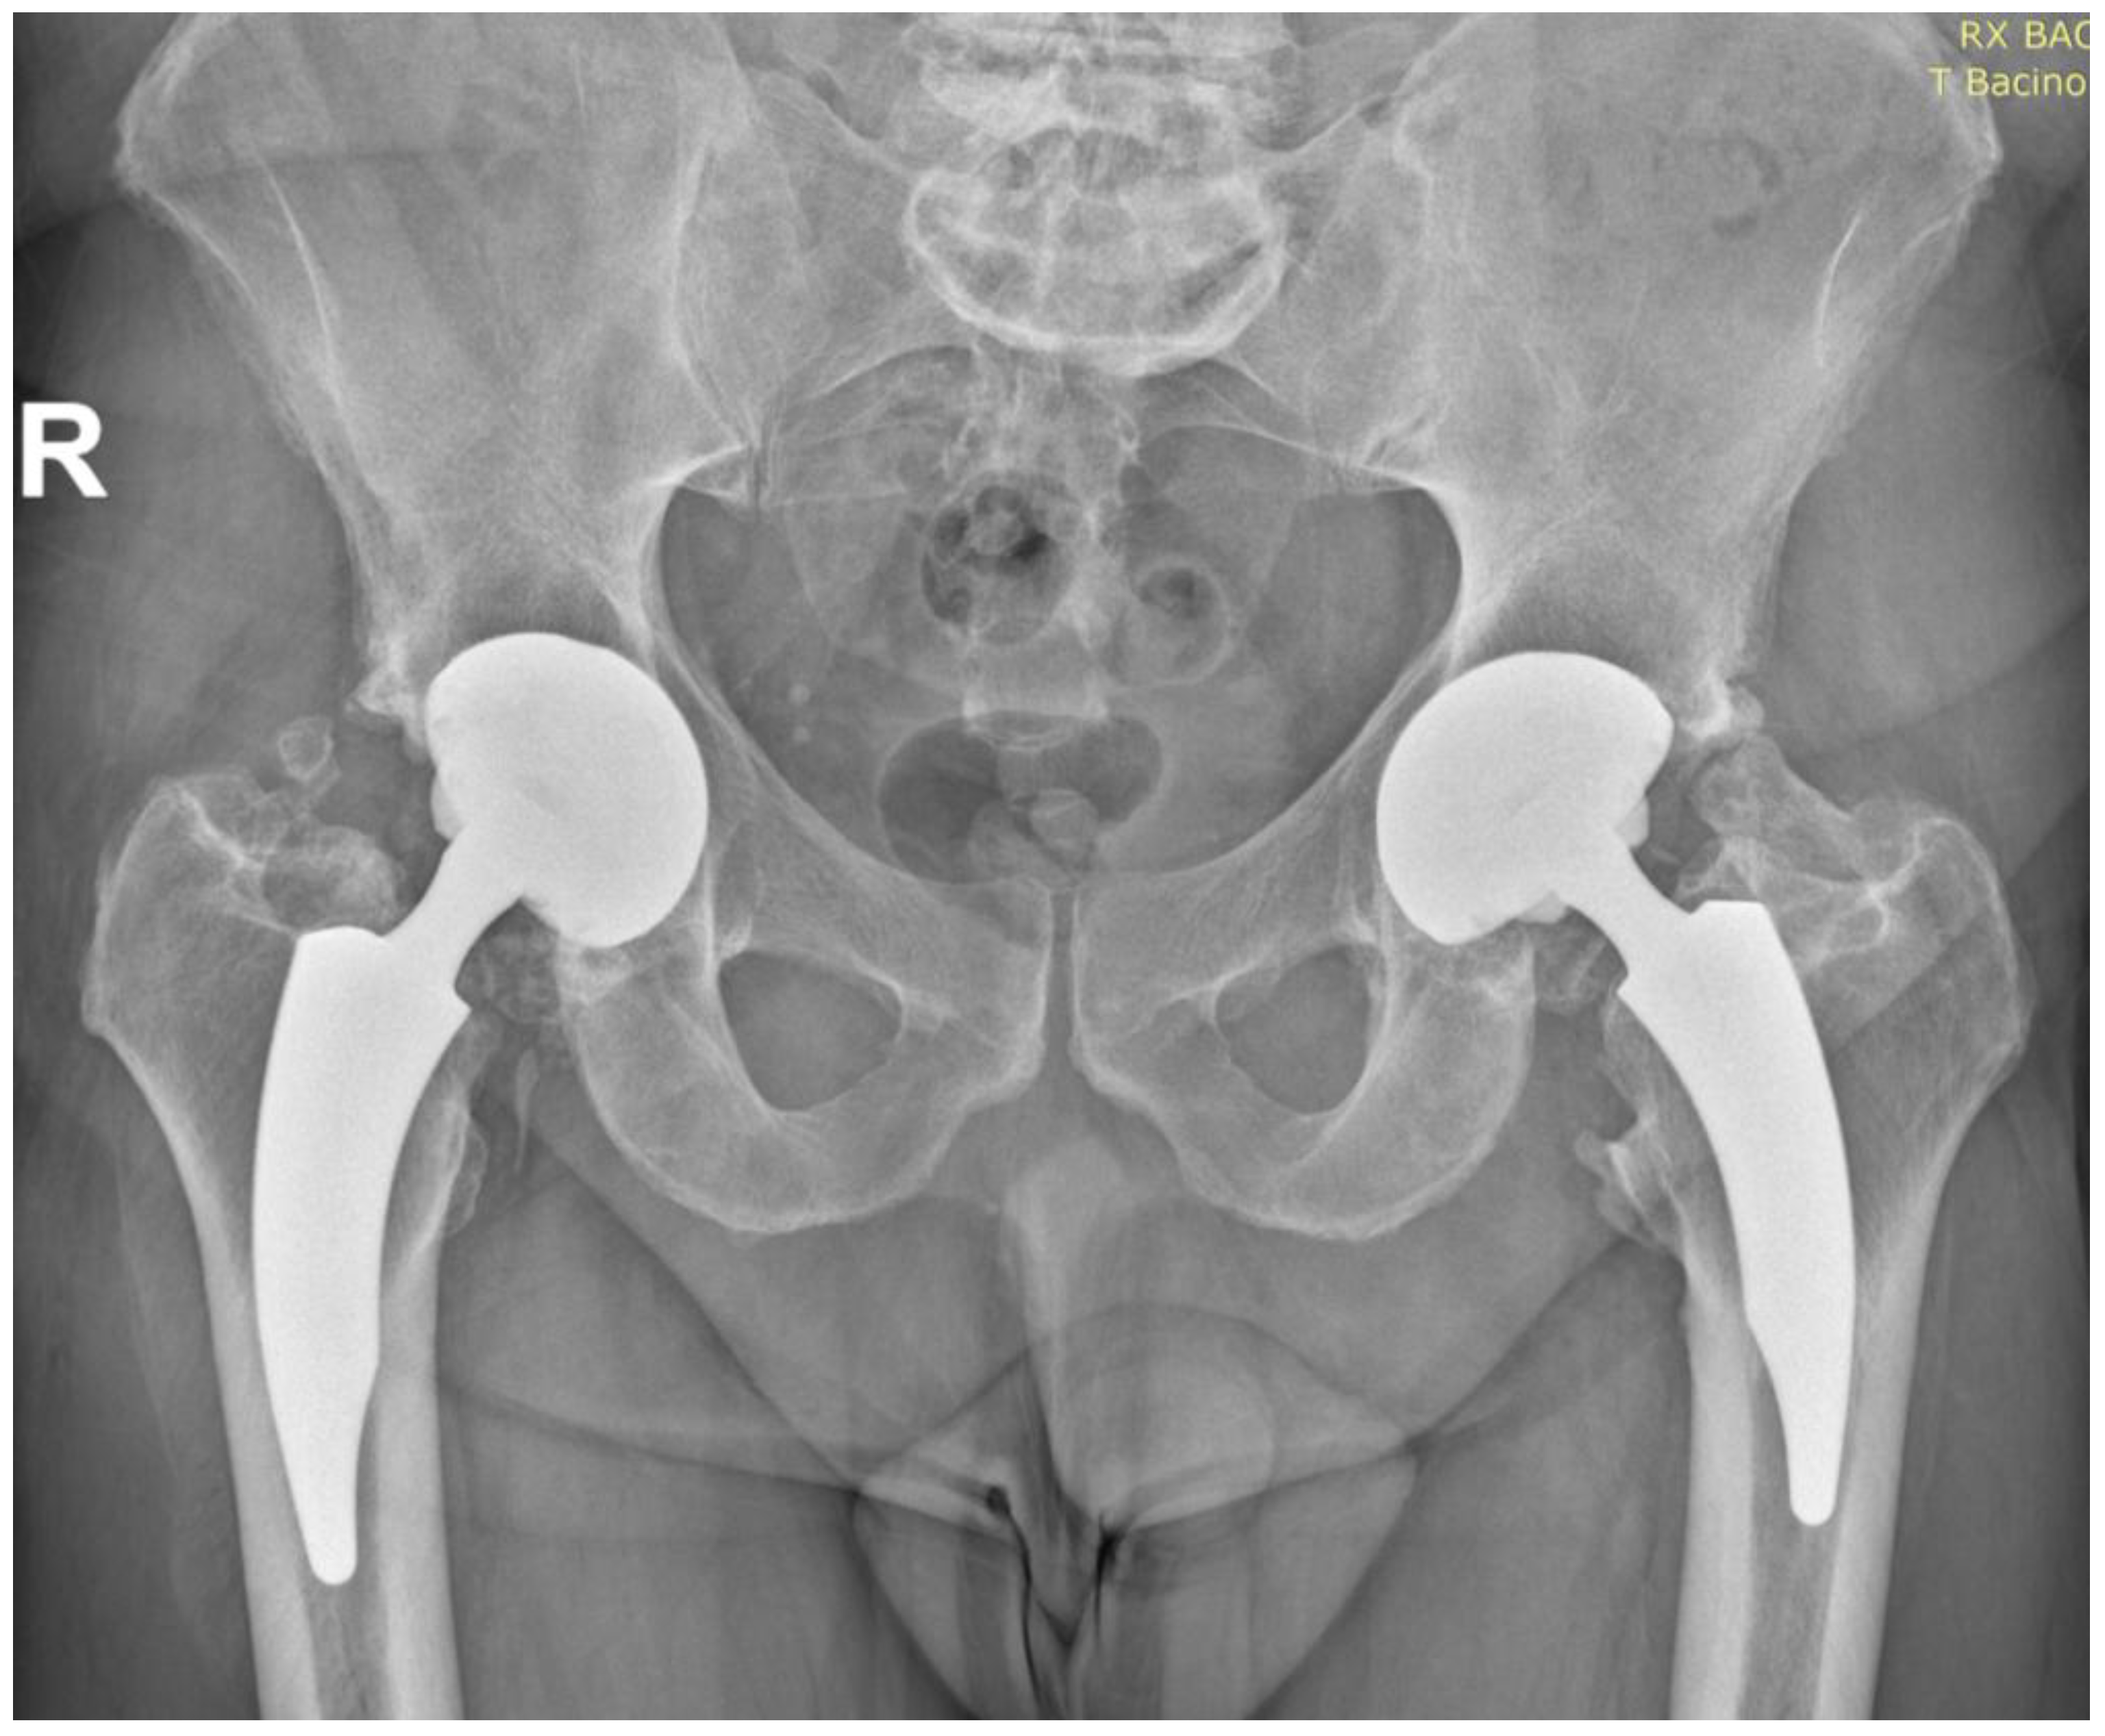

Fifteen-Year Follow-Up of Nanos Neck-Preserving Hip Arthroplasty: An Observational Retrospective Study

3.3. Radiographic Outcomes

- Implant Stability

| Radiographic Parameters | Value |

|---|---|

| Acetabular inclination | 44.6° |

| Leg Length Discrepancy | 2.7 mm |

| Femoral offset | 46 mm |

| Osteolysis (Gruen zones). | None |

| Heterotopic Ossification (Grade I–II) | 5 patients (9.4%) |

| Heterotopic Ossification (Grade III–IV) | 2 patients (3.8%) |